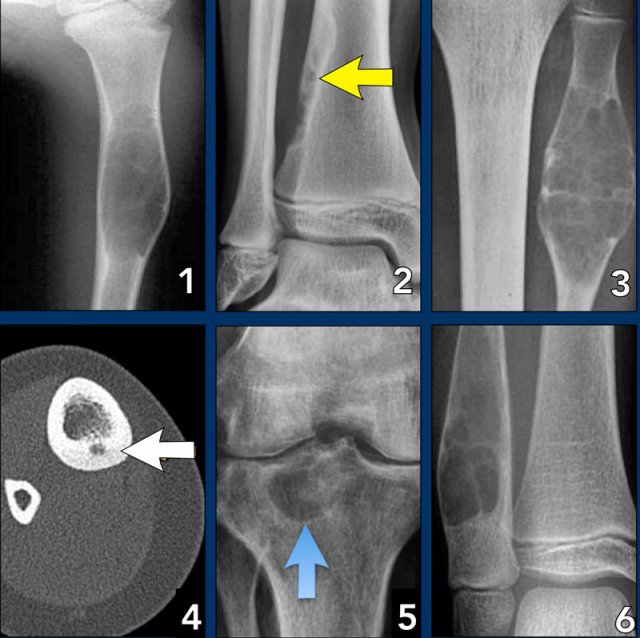

Benign periosteal reaction

Detecting a benign periosteal reaction may be very helpful, since malignant lesions never cause a benign periosteal reaction.

A benign type of periosteal reaction is a thick, wavy and uniform callus formation resulting from chronic irritation.

In the case of benign, slowly growing lesions, the periosteum has time to lay down thick new bone and remodel it into a more normal-appearing cortex.

Image

Benign periosteal reaction in an osteoid osteoma.

Large arrow indicates solid periosteal reaction.

Small arrow indicates nidus.

Aggressive periosteal reaction

This type of periostitis is multilayered, lamellated or demonstrates bone formation perpendicular to the cortical bone.

It may be spiculated and interrupted - sometimes there is a Codman's triangle.

A Codman's triangle refers to an elevation of the periosteum away from the cortex, forming an angle where the elevated periosteum and bone come together.

In aggressive periostitis the periosteum does not have time to consolidate.

Aggressive periosteal reaction Aggressive periosteal reaction

Aggressive periosteal reaction (2)

1. Osteosarcoma with interrupted periosteal rection and Codman's triangle proximally (red arrow).

There is periosteal bone formation perpendicular to the cortical bone and extensive bony matrix formation by the tumor itself.

2. Ewing sarcoma with lamellated and focally interrupted periosteal reaction. (white arrows)

3. Infection with a multilayered periosteal reaction.

Notice that the periostitis is aggressive, but not as aggressive as in the other two cases.

Osteosarcoma (left) and Ewings sarcoma (right) Osteosarcoma (left) and Ewings sarcoma (right)